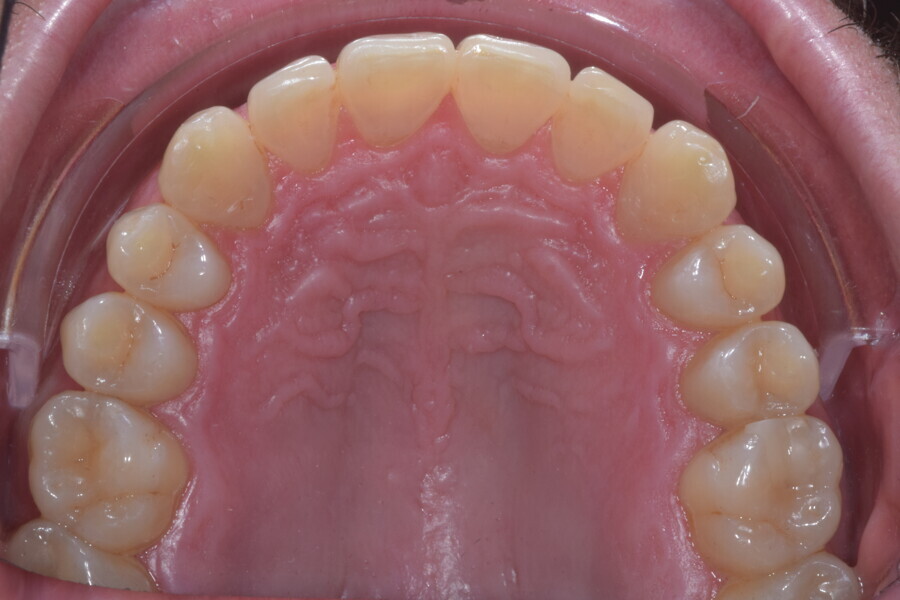

Fig. 13

Fig. 14

Fig. 15

Fig. 16

Fig. 17

Fig. 18

A 37-year-old male patient presented with the chief need for re establishing anterior alignment in both arches. Facial analysis showed a short face with a flat profile but proper chin projection (Figs. 9–12), and clinical examination revealed a skeletal Class I (ANB = 0.89°) and dental Class I malocclusion with severe deep bite (almost 100%), a deep curve of Spee, normal maxillary central incisor torque (Ui–FH = 110°), mild maxillary crowding and moderate mandibular crowding (Figs. 13–18). The deep bite components were represented in this patient by the severe skeletal condition of hypo divergent pattern (FMA = 14.24°) with normal maxillary and mandibular incisor inclination and decreased gonial angle (110.46°). Analysis of the cephalometric radiograph indicated a reduced lower anterior facial height, combined with a hypo-divergent pattern (Fig. 19). The only treatment option suggested was orthodontic treatment with aligners for deep bite correction with all the features described (bite ramps, pressure area, 3D curve of Spee levelling, Class II elastics and heavy occlusal contacts).